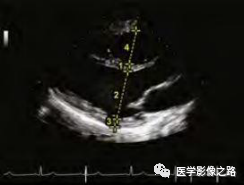

⑵三尖瓣环收缩期位移(TAPSE):四腔心切面,M型超声测量三尖瓣环侧壁的舒张期到收缩期的位移距离,<16mm为减低